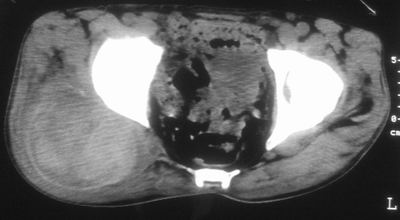

标题: CT16837:M63Y,右臀部巨大软组织包块

患者,男,63岁,自诉3个月前发现右臀部包块,触及疼痛,治疗后缩小。前天突然增大。无高热病史。

病灶内部可见出血,首先考虑急性出血性病变.血肿?

给个骨窗,判断一下肿块是否与髂骨有关,肿块内出血是肯定的,至于是感染形成的脓肿还是起源于肌肉或纤维组织的肉瘤则难以确定,不过从影像上看,包膜完整,且环形增厚,病灶下部见斑片状底密度坏死,个人倾向感染可能性大

考虑脓肿,建议增强扫描

肌间隙明显混浊,三个月前治疗有缩小,支持考虑臀大肌下脓肿伴出血,肿瘤如果出现瘤内出血的话瘤外边界应该较清楚,现在表现为一种恶性征像,但骨质无明显异常,且臀小肌边界清楚,不符合恶性表现.